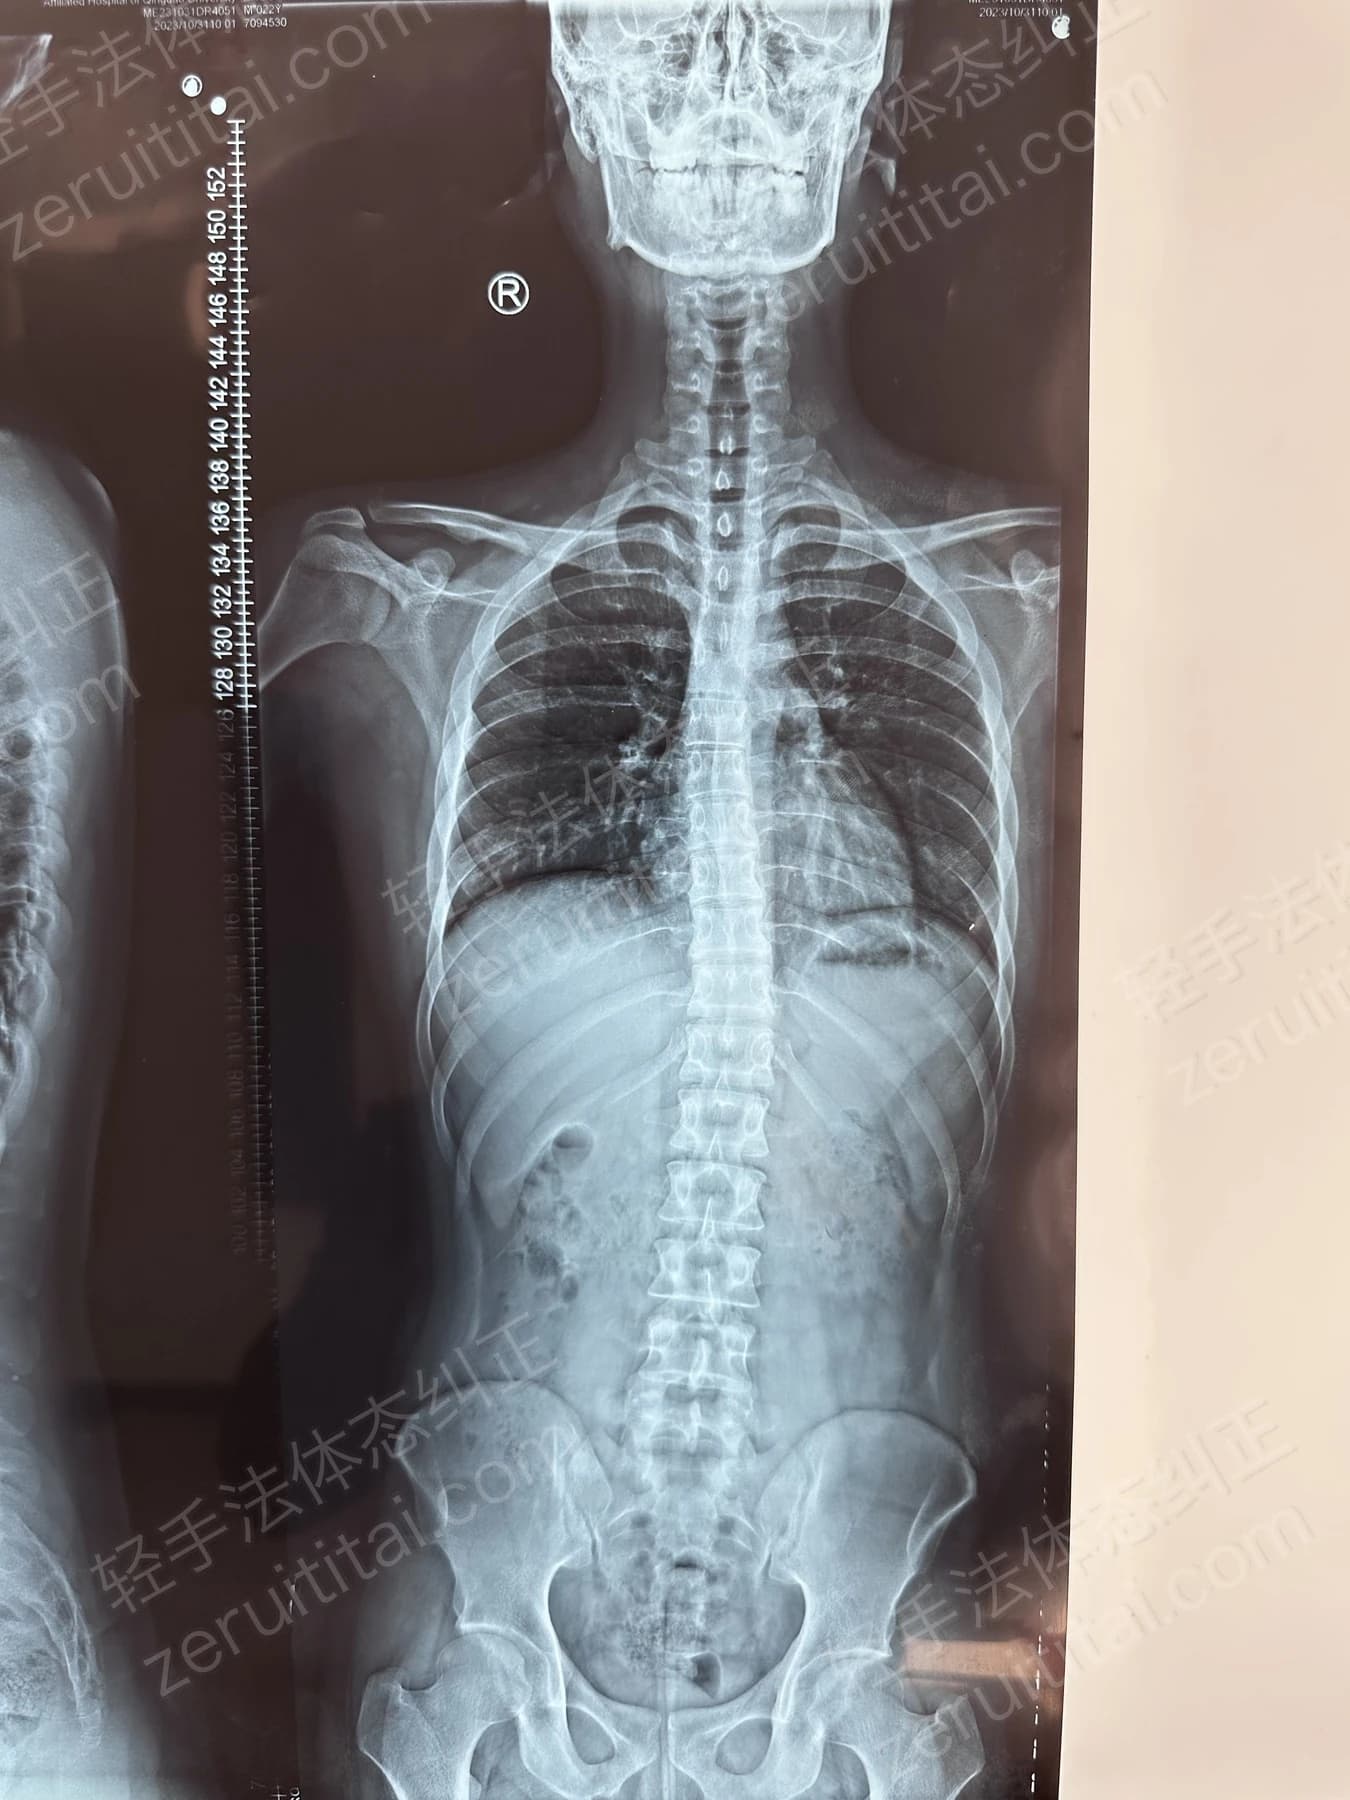

2022.06.27

第 1 次记录

第 1 次记录2022.06.27

正面 X 光